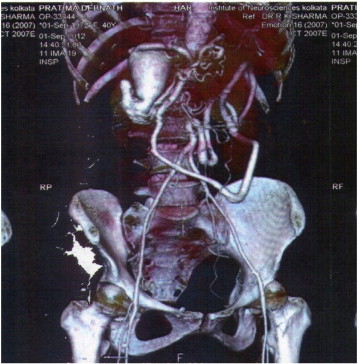

CT angiography showed agenesis of abdominal aorta from origins of renal arteries, abnormal branching of superior mesenteric artery forming vascular loop and reconstituting lower aorta, and large aneurismal dilatation of the distal part of the gastroduodenal artery (Fig. 1).

CT angiography showing agenesis of abdominal aorta, collaterals reconstituting ...

CT angiography showing agenesis of abdominal aorta, collaterals reconstituting the lower abdominal aorta and the aneurysm from gastroduodenal artery.